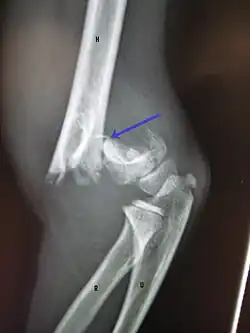

Distal

Distal humerus fractures usually occur as a result of physical trauma to the elbow region. If the elbow is bent during the trauma, then the olecranon is driven upward, producing a T- or Y-shaped fracture or displacing one of the condyles.[7]

Definitive diagnosis of humerus fractures is typically made through radiographic imaging. For proximal fractures, X-rays can be taken from a scapular anteroposterior (AP) view, which takes an image of the front of the shoulder region from an angle, a scapular Y view, which takes an image of the back of the shoulder region from an angle, and an axillar lateral view, which has the patient lie on his or her back, lift the bottom half of the arm up to the side, and have an image taken of the axilla region underneath the shoulder.[9] Fractures of the humerus shaft are usually correctly identified with radiographic images taken from the AP and lateral viewpoints.[12] Damage to the radial nerve from a shaft fracture can be identified by an inability to bend the hand backwards or by decreased sensation in the back of the hand.[5] Images of the distal region are often of poor quality due to the patient being unable to extend the elbow because of pain. If a severe distal fracture is suspected, then a computed tomography (CT) scan can provide greater detail of the fracture. Nondisplaced distal fractures may not be directly visible; they may only be visible due to fat being displaced because of internal bleeding in the elbow.[7]

Fractures of the humerus are classified based on the location of the fracture and then by the type of fracture. There are three locations that humerus fractures occur: at the proximal location, which is the top of the humerus near the shoulder, in the middle, which is at the shaft of the humerus, and the distal location, which is the bottom of the humerus near the elbow.[9] Proximal fractures are classified into one of four types of fractures based on the displacement of the greater tubercle, the lesser tubercle, the surgical neck, and the anatomical neck, which are the four parts of the proximal humerus, with fracture displacement being defined as at least one centimeter of separation or an angulation greater than 45 degrees. One-part fractures involve no displacement of any parts of the humerus, two-part fractures have one part displaced relative to the other three; three-part fractures have two displaced fragments, and four-part fractures have all fragments displaced from each other.[13][14][3] Fractures of the humerus shaft are subdivided into transverse fractures, spiral fractures, "butterfly" fractures, which are a combination of transverse and spiral fractures, and pathological fractures, which are fractures caused by medical conditions.[12] Distal fractures are split between supracondylar fractures, which are transverse fractures above the two condyles at the bottom of the humerus, and intercondylar fractures, which involve a T- or Y-shaped fracture that splits the condyles.[7]